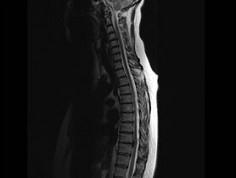

问题 男,65岁,背部疼痛2个月余,MRI检查如图,请选出最可能的诊断 ( )

选项 A、硬膜外纤维化 B、神经根鞘囊肿 C、椎管内肿瘤 D、椎间盘突出 E、椎间盘炎

答案 D